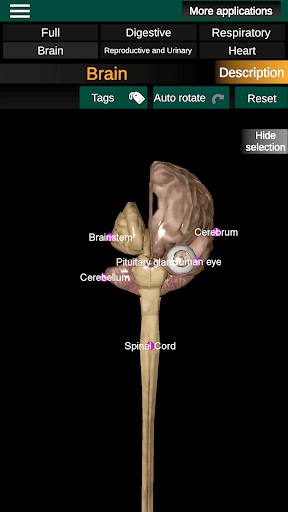

* Мозок, який включає головний мозок, мозочок і стовбур мозку.